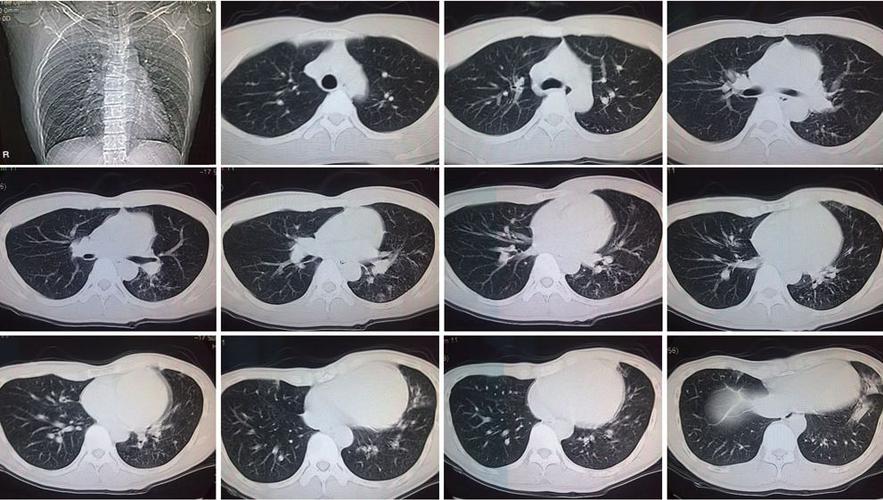

正常的肺部ct图片 讲解

正常的肺部ct图片 讲解,肺部ct图片讲解解读

肺部ct图片讲解解读

肺部ct图片讲解

正常肺部ct怎么看图解

肺部ct怎么看图解解读

肺部ct图解

肺部ct怎么看图解